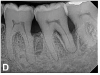

(9.) Progressive improvement in bone quality, quantity, and morphology during each time period, especially in the furcation area of tooth No. 18, which shows a noticeable narrowing of the width of the bony defects, slight apical resorption of the distal root of tooth No. 18, and the encasing of residual cementum on the distal root of No. 19 by new bone formation. Periapical radiographs were taken of teeth Nos. 17, 18, and 19 on June 25, 2016, January 28, 2017, August 23, 2019, and September 4, 2020, respectively, the final of which was taken after almost 5 years post-initial scaling and root planing and alternating supportive periodontal maintenance.

Figure 9

(10.) Progressive improvement in bone quality, quantity, and morphology during each time period, especially in the furcation area of tooth No. 18, which shows a noticeable narrowing of the width of the bony defects, slight apical resorption of the distal root of tooth No. 18, and the encasing of residual cementum on the distal root of No. 19 by new bone formation. Periapical radiographs were taken of teeth Nos. 17, 18, and 19 on June 25, 2016, January 28, 2017, August 23, 2019, and September 4, 2020, respectively, the final of which was taken after almost 5 years post-initial scaling and root planing and alternating supportive periodontal maintenance.

Figure 10

The patient's periodontal disease improved with initial nonsurgical periodontal therapy that involved scaling and root planing. This initial treatment was followed by only SPT every 3 months. Despite treatment, residual deep periodontal probing depths remained, so a decision was made to maximize improvements with nonsurgical therapy and to reassess as needed to determine whether surgical intervention was appropriate. After almost 5 years of SPT and good patient compliance with plaque control and supportive care, the periodontium was stable. Because of the resulting bone formation and improvements in clinical attachment levels (Figure 7 through Figure 13), it was determined that periodontal surgical intervention was not necessary.

In the case report presented, treatment with nonsurgical therapy for 5 years effectively halted destruction and led to bone regeneration and improved clinical attachment levels. Although the primary etiology of periodontal disease is well documented, secondary etiologic and contributing factors are numerous.16 After initial therapy in the current case, there was radiographic evidence of a hypercementosis-like lesion on the distal root of tooth No. 19 (Figure 7 through Figure 10). Hypercementosis is a nidus for plaque accumulation leading to disease progression; however, the presence of this lesion did not explain the disease severity observed for tooth No. 18. Chronic periodontitis is the most widespread form of periodontal disease, and nonsurgical periodontal therapy is the most common type of therapy.17 Scaling and root planning is the gold standard for periodontal treatment. When performed meticulously, they result in improvement of clinical parameters through changes related to tissue shrinkage, long junctional epithelium, new attachment, and in rare circumstances, regeneration.18 The use of nonsurgical periodontal therapy for treatment of periodontal disease requires that the timing for re-evaluation is customized for each patient. Because individuals heal at different rates, the overall medical condition, nutritional intake, environmental and social risks factors, local factors, and colonization of pathogenic bacteria of patients should be considered.7,8 Some patients cannot afford, or choose not to pursue, surgical periodontal therapy. For these patients, clinicians should delay surgical decisions until periodontal risk factors are addressed and nonsurgical efforts are exhausted.

Although rare, the radiographic evidence in the current case indicated that nonsurgical therapy effectively halted the destructive effects of severe chronic periodontitis and led to bone regeneration, thereby eliminating the need for surgery. The current case also showed that nonsurgical periodontal therapy may lead to desirable outcomes for patients with severe chronic periodontal disease if the patient is compliant with plaque control, supportive periodontal therapy is provided, etiological and risk factors are eliminated, and the body is given adequate time to heal.11 An additional factor that may have influenced the positive outcome of the current case was the patient's favorable health status.